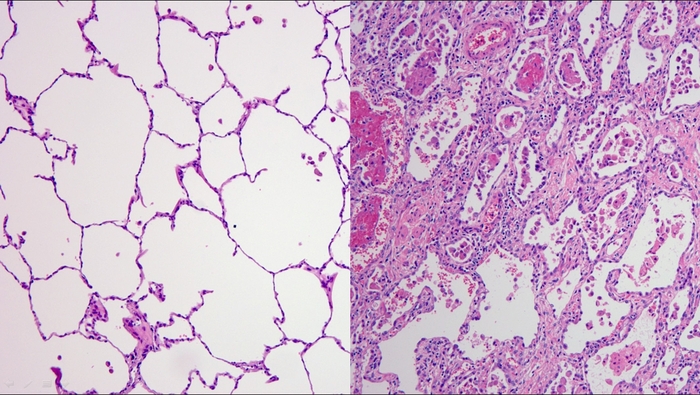

에크모센터장 흉부외과 김형수 교수는 “코로나19 환자 중 국내에서 최고의 중증치료 사례였으며 코로나바이러스에 감염된 폐를 떼어낼 때 건강한 폐와 다르게 크기도 작게 수축 되었고 마치 돌덩이처럼 폐가 딱딱한 느낌이었다”며 “건강하고 젊은 코로나19 감염증 환자도 폐섬유화 진행 속도가 빨라 폐이식까지 갈 수 있으니 젊다고 방심하지 말고 감염을 막기 위한 사회적 거리두기, 마스크 착용 등의 노력을 지속해야 한다”고 했다.

에크모센터 호흡기내과(중환자의학) 박성훈 교수는 “코로나19 환자의 특징은 영상검사에서는 잘 나타나지 않았지만 실제로 폐섬유화 진행속도가 빨라 자칫 놓칠 수도 있어 환자 관찰이 중요하다”며 “현재까지 환자가 급성거부반응을 나타나지는 않았다. 이를 유지하기 위해 다학제 진료를 통해 환자의 건강상태를 면밀하게 파악하고 급성거부반응의 위험성을 낮추기 위해 면역억제제 농도를 조절하고 재활운동에 집중하고 있다”고 설명했다.